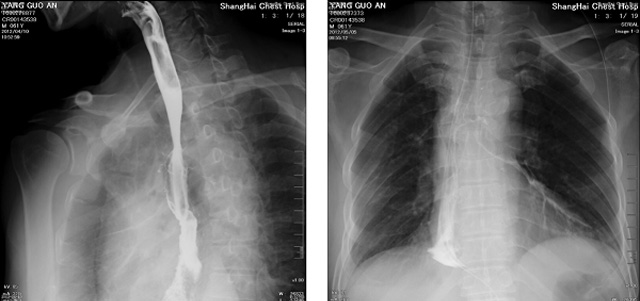

DR設(shè)備在2020年的新冠疫情中,加速了市場(chǎng)調(diào)整。以醫(yī)院為主的向二三級(jí)市場(chǎng)轉(zhuǎn)變。特別是小巧靈活的移動(dòng)DR設(shè)計(jì),填補(bǔ)CT和磁共振不能三維檢查的缺點(diǎn),滿足內(nèi)科外科特別是骨科的影像診斷需求。還有懸吊DR設(shè)備CT斷層射線系統(tǒng)。使用錐束成像技術(shù)對(duì)整個(gè)脊柱和整個(gè)下肢進(jìn)行了體積三維掃描。無(wú)需使用對(duì)比劑,即可使用X射線呼吸功能標(biāo)測(cè)來(lái)模擬模擬氣流和血流,以評(píng)估患者的肺動(dòng)脈血栓。